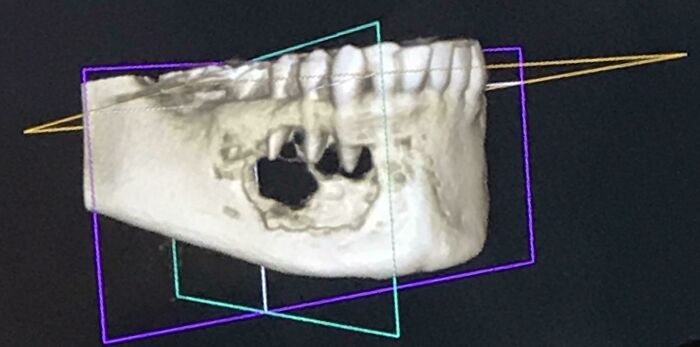

Went In For Teeth Cleaning Last Month And Mentioned A Numb Feeling In A Tooth- I Was Shocked To Find A Tumor Eating My Jaw Bone

This photo is my CT scan. Biopsy surgery results were non-cancerous, thankfully. It’s been a real WTF month.